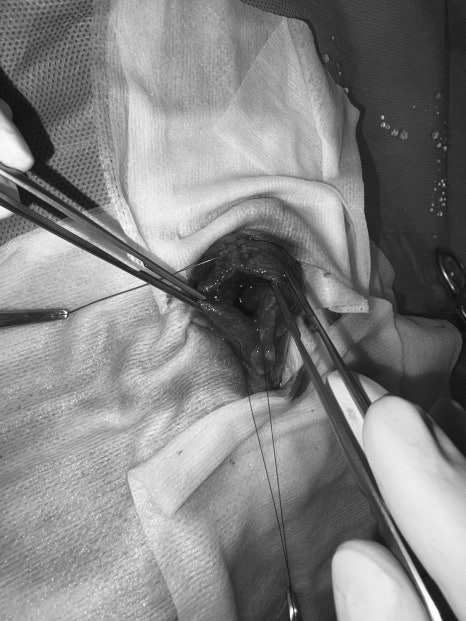

수술은 원장님이 직접 집도하였으며, 방광을 절개해 내부 결석을 모두 제거했습니다.

방광 절개 후 결석을 모두 제거한 뒤, 봉합 부위의 밀폐 상태를 확인하기 위해 ‘Leakage test’를 진행했습니다.

방광 안에 식염수를 주입해 누출이 없는지 꼼꼼히 확인했으며, 정상적으로 봉합이 잘 이루어진 것을 확인했습니다.